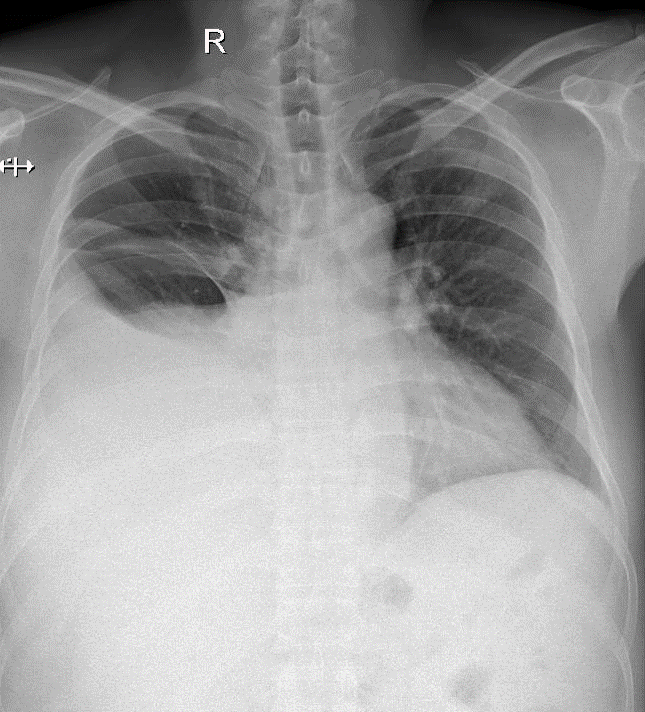

Hãy phân tích tình huống Nam 58 tuổi

1-Tràn dịch màng phổi (P) lượng nhiều